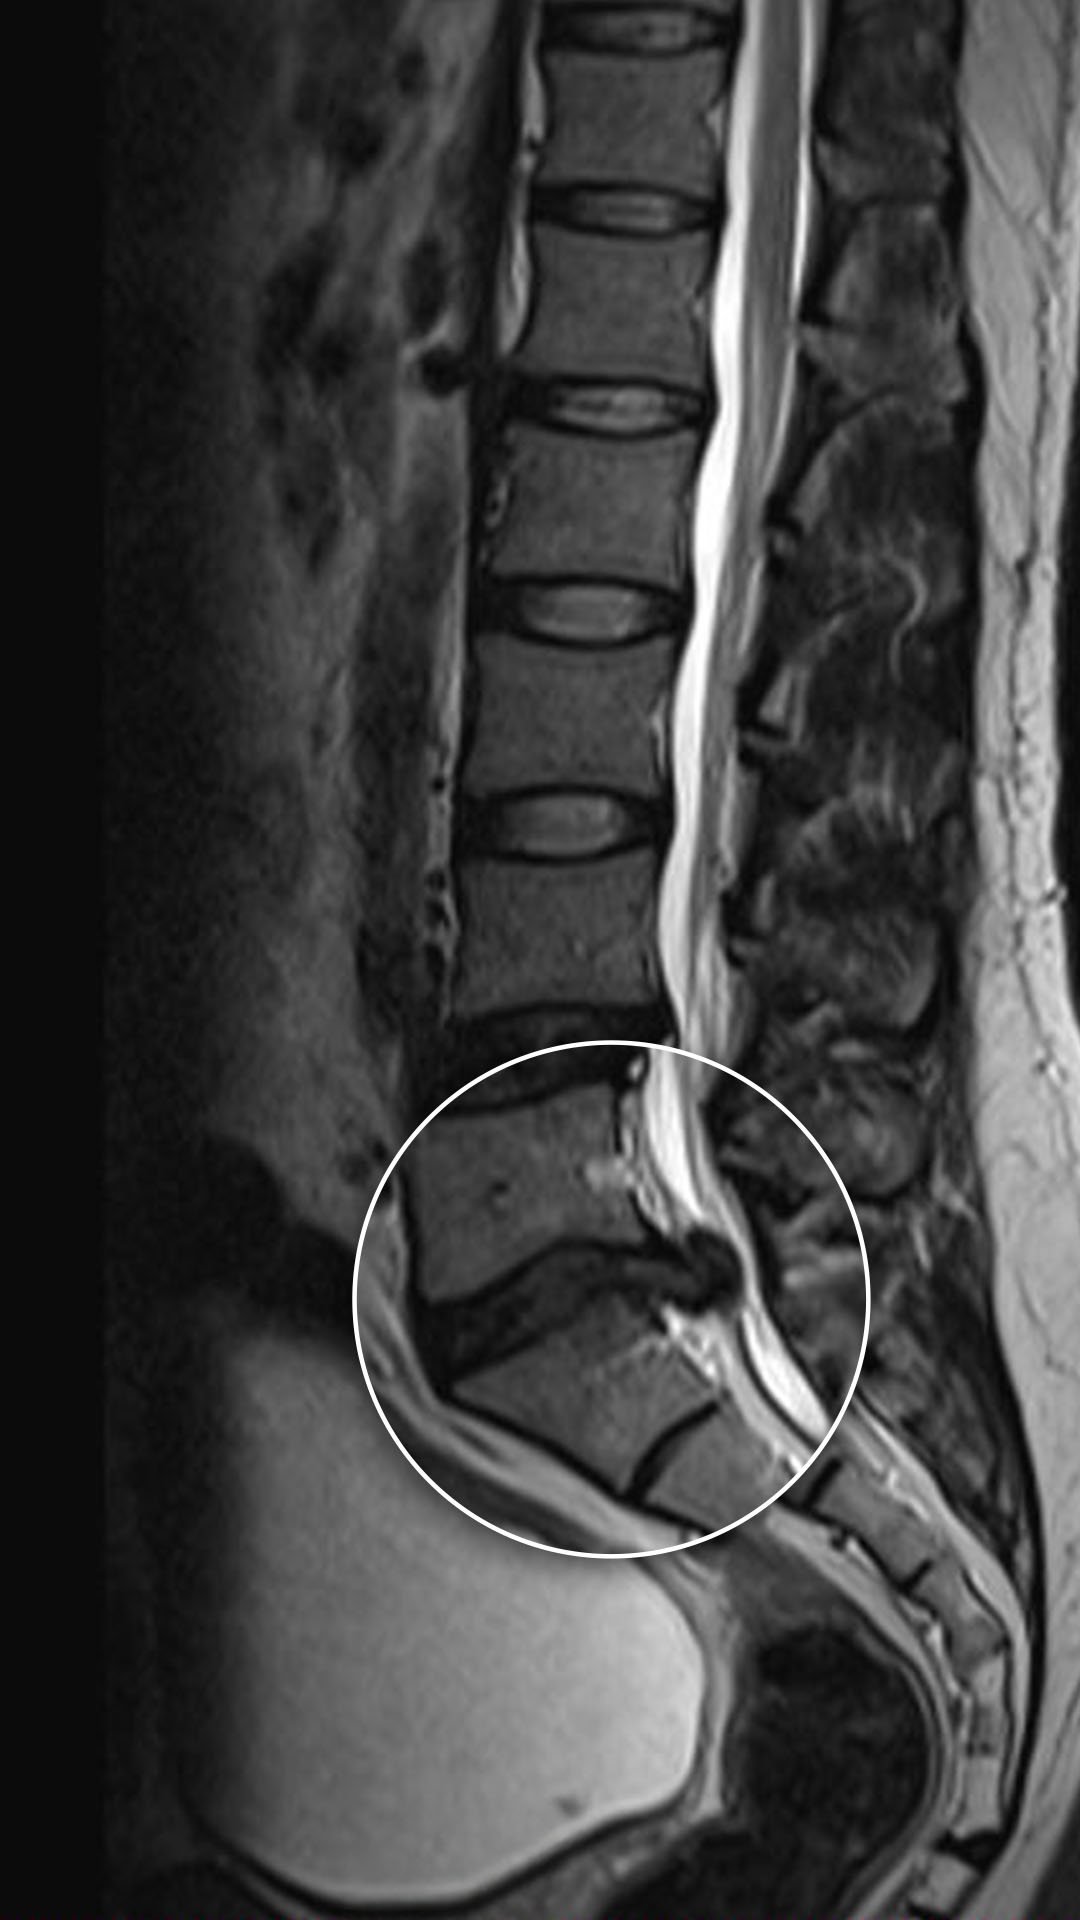

صور الأشعة لمريضتنا العزيزة كورتيلينا توضّح حالة الديسك بين الفقرة القَطَنية الخامسة والعجزية الاولى .

تم إجراء عملية إزالة الانزلاق الغضروفي وتحرير الضغط عن العصب، باستخدام تقنيات دقيقة في التدخل الجراحي المحدود، والنتيجة كانت استعادة استقرار الفقرات واختفاء الألم بالكامل خلال أيام قليلة، وبجرح صغير لا يتجاوز الـ1.5سم.